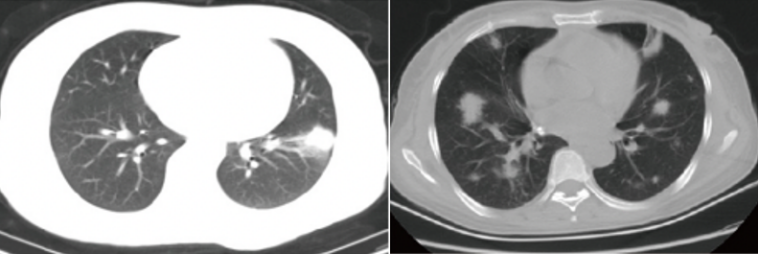

IPA的CT影像学有多种表现,从非特征性的气道病变逐渐演变为特征性的血管侵袭为主[4]。曲霉菌侵袭累及肺泡和细支气管壁,影像学可呈现非特征性改变如支气管周围实变影、支气管扩张征、小叶中心型微小结节影、树芽征和磨玻璃样改变等表现,为曲霉菌气道侵袭特征性表现。IPA特征性CT影像学包括:致密、边界清楚的病变(伴或不伴晕征)、空气新月征、空洞、楔形/节段性或大叶性病灶[1]

IPA患者可出现特征性或非特征性CT改变,且疾病不同阶段CT表现存在一定差异。IPA患者的CT表现与免疫缺陷类型或程度及潜在宿主疾病相关,严重免疫抑制时免疫反应极为有限;而免疫恢复/重建时,反应将增加、病变可能会扩大。边界清晰的病变(结节)是IPA的主要影像学表现;不同影像学表现可能代表疾病的不同阶段[5]。针对免疫缺陷患者,IPA的CT特征随疾病进展而有不同表现:疾病早期以晕轮征为主,随后以空气新月征、空洞常见[6];此外,患者初期病变数量及大小增加,随后进入减少的平稳阶段[7]

IPA患者还可表现为非特异性和不常见的CT改变,如实变、空洞性病变、胸腔积液、磨玻璃样混浊、树状浸润性病变和肺不张等,但非特异性CT可能会进展为特异性表现。IPA的特异性征象包括:小结节(<10 mm)、树芽征、磨玻璃病变、气腔实变等。病理基础为曲霉菌侵袭气道致气腔内渗出,影像上不具有特异性,细菌、病毒感染均可出现这些征象。真菌感染非特异性征象出现概率较小,其原因可能是机体免疫力提高或抗真菌治疗使病变很快被吸收或迅速进展为血管侵袭期,所以出现时间短。

IPA的特征性影像:①大结节:>10 mm,影像特点:一般双肺多发,形态不规则,边缘毛糙,可有分叶,倾向于中上肺野分布;病理基础:血管侵袭期形成炎性肉芽肿,中心凝固性坏死。②晕征:影像特点为结节周围见模糊淡薄磨玻璃渗出,边界不清。病理基础:病变侵袭血管致血管出血,渗出至结节周围形成“晕征”。渗出短时间内吸收,因此“晕征”出现的时间也较短。③空洞:影像特点为多态结节内出现空洞,部分空洞内见细网状分隔或结节(形成空气半月征)。病理基础:机体免疫力提高或抗真菌治疗有效,菌丝被切断,原本被菌丝抓住的凝固性坏死物质逐渐排出,当部分排出时,空洞内残留部分菌丝及坏死物质,即形成网状分隔;若空洞内残留菌丝及坏死物质形成结节,结节与空洞之间形成“空气半月征”;若坏死物质全部排出即形成空洞。

图片

结节

晕征

空洞

非免疫缺陷患者中IPA的非特征性CT改变同样较为常见,应引起临床关注。气道侵袭性CT症状亦是IPA患者的常见表现,且动态监测有助于早期识别IPA患者。一项对254例成人侵袭性肺曲患者的研究,患者表现为多种血管侵袭症状及多种气道侵袭症状;研究同时发现:非免疫功能缺陷IPA患者中,仅28.9%的患者早期表现为血管侵袭症状,但随疾病进展越来越常见;相对,几乎所有患者在疾病开始时都表现出气道侵袭症状[8]